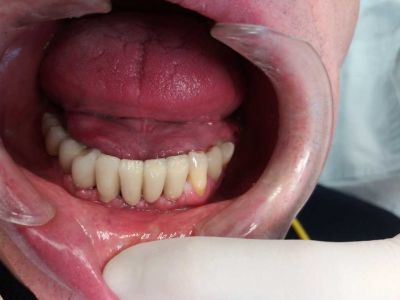

Il paziente è arrivato alla nostra attenzione con problemi gengivali ed elevata mobilità dei denti frontali inferiori, che li rendeva purtroppo non più recuperabili.

PRIMA

Dall'inizio del trattamento alla consegna del lavoro definitivo il paziente ha sempre utilizzato un provvisorio fisso.